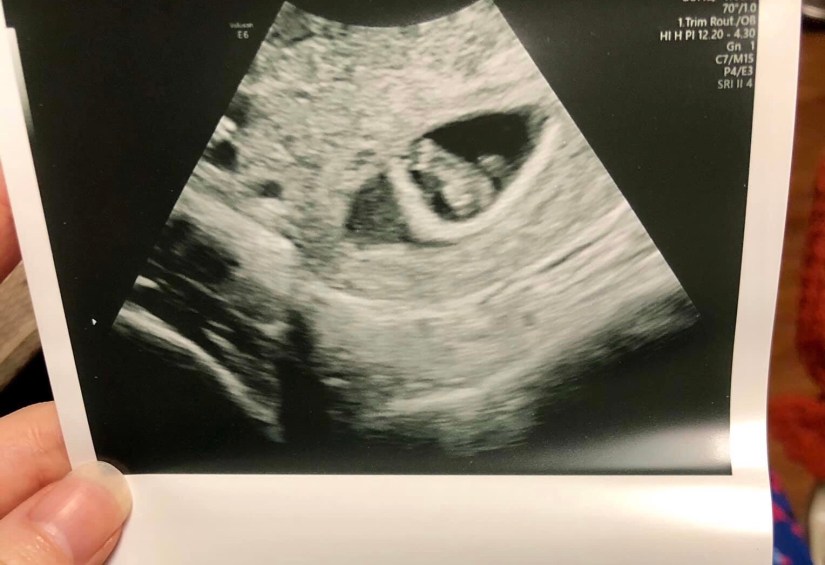

Everything was going well! We went to our first prenatal appointment and we saw a strong heart rate of 133. The baby was measuring right on track, and the doctor gave us a due date for Christmas Day. Wow, I thought, how special! Christmas is special for many reasons, the main one being that it’s the day we celebrate the birth of Jesus Christ. Not only that, but my grandma was born on Christmas Day also. I wrote a poem about her last week titled, Catharine Rose. I was very close to her, and still miss her so much. I was looking forward to our son or daughter sharing a birthday with her, and even had the plan to name our baby Catharine Rose Stout had it been a girl. I was finally allowing myself to feel excited, Jeremy and I couldn’t wait!